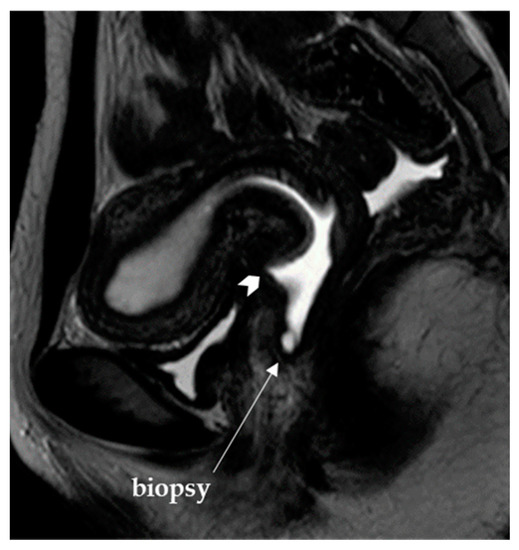

Congenital Obstructive Müllerian Anomaly: The Pitfalls of a Magnetic Resonance Imaging-Based Diagnosis and the Importance of Intraoperative Biopsy

Kim, D.Y.; Nam, G.; Lee, S.R.; Kim, S.H.; Chae, H.D.; Kang, B.M. Congenital Obstructive Müllerian Anomaly: The Pitfalls of a Magnetic Resonance Imaging-Based Diagnosis and the Importance of Intraoperative Biopsy. J. Clin. Med. 2021, 10, 2414. https://doi.org/10.3390/jcm10112414